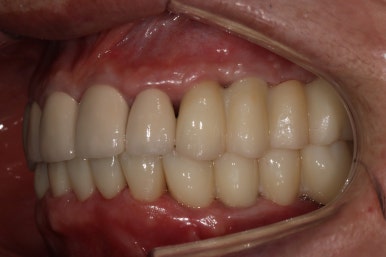

그렇게 완성된 최종 보철물 형태입니다.

임시치아와 다르게 지르코니아 크라운으로 제작되어 훨씬 단단하고 매끈하고 이상적인 형태를 가진걸 보실 수 있으실거에요.

위 아래 앞니 모두 적절한 길이로 회복이 되었고, 어금니도 이상적인 형태를 보여주고 있습니다.

좌우로 옆에서 봤을 때도 충분히 기능이 잘 되게끔 잘 물리는 어금니를 보실 수 있을거에요.

식사 시 음식이 덜 끼도록 치아와 치아사이를 최대한 닫아놓은 모양입니다.

위아래 모두 아주 이상적인 형태로 제작된 치아모양의 지르코니아 크라운을 보실 수 있을거에요.

이 정도면 전체 구강 재건 (full arch rehabilitation)이라고 불러야 합니다.